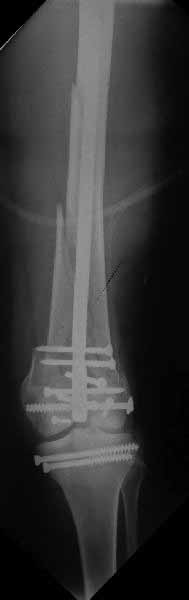

Ответ на эту часть Вашего поста – вложенный файл. Больная оперирована неделю назад по поводу открытого перелома дистального эпиметафиза бедренной кости. После операции она идёт в рентгенкабинет для выполнения послеоперационной контрольной рентгенографии, представленной на слайдах 10 и 11. Узнав, почему её фотографируют, просила передать Вам, Антон, привет.

наружный мыщелок не дорепонироавн - это приводит к вальгусной деформации оси коленного сустава, очень критично для последующей функции.